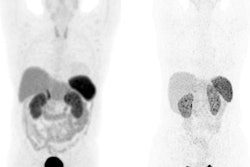

The researchers performed automated body composition analysis on 74 consecutive GEP-NET patients who had received whole-body gallium-68 (Ga-68) DOTATOC PET/CT exams as well as BIA and DEXA scans between February 2019 and October 2021. The deep-learning model was applied to the contrast-enhanced, 5-mm, whole-body CT images for all 74 patients.

The model examined seven volumes for different body compartments and quantified subcutaneous adipose tissue, visceral adipose tissue, intermuscular adipose tissue, epicardial adipose tissue, and paracardial adipose tissue. Muscular and bone tissue volumes were computed to generate a skeletal muscle ratio and body fat ratio.